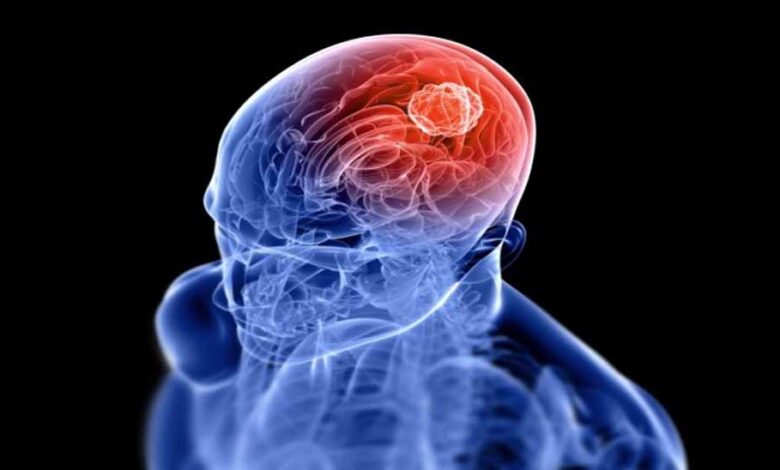

मेडिकल हब बन चुके इंदौर में अब गंभीर बीमारियों का इलाज आधुनिक तकनीकों के माध्यम से किया जा रहा है। ब्रेन ट्यूमर बीमारी का इलाज शासकीय एमवाय अस्पताल और निजी अस्पतालों में आधुनिक तकनीकों से किया जा रहा है, लेकिन आवश्यक है कि मरीज समय पर इसके लक्षण पहचानकर इलाज करवाएं।

विशेषज्ञों ने बताया कि ब्रेन ट्यूमर के मरीजों की संख्या हर वर्ष बढ़ रही है। इसका एक प्रमुख कारण यह है कि अब जांच की सुविधाएं छोटे शहरों और तहसीलों तक पहुंच चुकी हैं। पहले जहां मरीजों को जांच के लिए बड़े शहरों का रुख करना पड़ता था, वहीं अब सिटी स्कैन और एमआरआई जैसी आधुनिक जांच तकनीकें छोटे जिलों में भी उपलब्ध हैं। इस कारण बीमारी का पता जल्दी लग जाता है और समय पर इलाज शुरू हो पाता है। पहले जहां लोग इसका इलाज कराने से बचते थे, लेकिन अब योजनाओं का लाभ लेते हुए बड़ी संख्या में मरीज इसका उपचार शासकीय और निजी अस्पतालों में करवा रहे हैं।

न्यूरोसर्जरी विभाग के एचओडी डॉ. राकेश गुप्ता ने बताया कि एमवाय अस्पताल में मरीजों को आधुनिक तकनीकों से इलाज मिल रहा है। हर वर्ष करीब 300 ब्रेन ट्यूमर के ऑपरेशन किए जाते हैं। जनवरी माह में अस्पताल में मरीज को बिना बेहोश किए ब्रेन ट्यूमर का ऑपरेशन किया गया था। यह ऑपरेशन अवेक क्रेनियोटामी पद्धति से किया गया था। अब मरीज स्वस्थ है। इसके अलावा स्पेशियलिटी अस्पताल में इंट्रा-ऑपरेटिव मॉनीटरिंग सिस्टम से मरीजों को उपचार की सुविधा मिल रही है। इससे ऑपरेशन की सफलता दर बढ़ गई है और मरीज जल्दी स्वस्थ हो जाते हैं। धार से आए मरीज ने बताया कि मुझे लगातार सिरदर्द और चक्कर आते थे। डॉक्टर ने एमआरआई करवाने के लिए कहा, जिसमें ब्रेन ट्यूमर की पुष्टि हुई। पहले डर लग रहा था, लेकिन डॉक्टरों ने समझाया कि अब इसका इलाज संभव है। मेरी सर्जरी हुई और अब मैं सामान्य जीवन जी रहा हूं।

इंदौर में आधुनिक तकनीकों से ब्रेन ट्यूमर के 95 प्रतिशत ऑपरेशन सफल हो रहे हैं। यही कारण है कि लोग भी अब इसके प्रति जागरूक होने लगे हैं। बात करें शहर के निजी अस्पतालों की तो यहां पर भी नई तकनीकों से इसका इलाज किया जा रहा है। न्यूरोसर्जन डॉ. रजनीश कछारा ने बताया कि पहले लोगों को लगता था कि ब्रेन ट्यूमर होने पर मरीजों के बचने की संभावना कम है, लेकिन अब आधुनिक तकनीकों के माध्यम से बेहतर इलाज मिलने लगा है। नेविगेशन से पता चल जाता है कि ट्यूमर कहां है। साथ ही आपरेशन के बाद भी मरीजों को आईसीयू जैसी सुविधाएं मिलने लगी हैं।

विशेषज्ञों के अनुसार, ब्रेन ट्यूमर के लक्षण उसके प्रकार, विकास की दर, स्थान और ट्यूमर की गंभीरता पर निर्भर कर सकते हैं। ब्रेन ट्यूमर के कुछ सामान्य लक्षण सिरदर्द (विशेष रूप से सुबह उठते ही), उल्टी और जी मचलाना, बोलने, सुनने या देखने की क्षमता में परिवर्तन, संतुलन बिगड़ना, याददाश्त कमजोर होना, थकान होना, दिनभर नींद आना, व्यवहार में परिवर्तन, मिर्गी के दौरे आना आदि हैं। यदि ऐसे कोई लक्षण दिखाई देते हैं तो तुरंत विशेषज्ञ से संपर्क करना चाहिए। ब्रेन ट्यूमर होने की कोई उम्र नहीं होती है। यह किसी भी उम्र में हो सकता है।